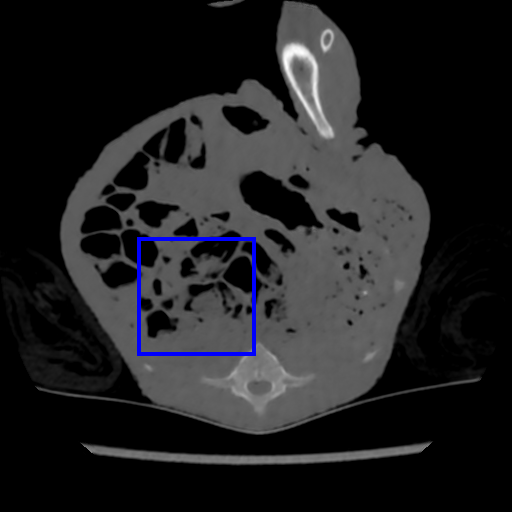

4.1 CT-Scan Denoising Evaluation

Task Generation. The CT database in [45] contains CT scans of a deceased piglet. The scans are produced using a normal dose of tube current (100%) and reduced doses. We use the doses of 10% and 5% because they include substantial amount of noise, where each dose set has 850 images of size . Following the data set protocol [45], 708 of those images are selected for training and 108 for testing. During training, each task consists of synthetic images generated by simulating reduced dose CT images by adding Poisson and Gaussian noise to the sinograms of the normal dose CT images, as in , where , , with denoting the Poisson distribution, representing the process to generate the sinogram or the fan-beam projected data [48] from the clean CT image , denoting the read-out electronic noise represented by the Gaussian distribution with mean and variance , and denoting the X-ray source intensity or a blank scan factor that controls the noise level. We create the tasks with , namely one per blank scan factor, where we use the following factors . Consequently, each factor contributes to the generation of a different task. To simulate the effect of the Gaussian noise, we add noise directly on the CT image . The Gaussian task is represented by Gaussian noise with , where denoting uniform distribution in . The result is the noisy image for and . Finally, we keep images for the meta-learning for each reduced dose set. The rest of the images are used for evaluation.

Model. We use a residual encoder-decoder architecture from [12] that has been proposed for low dose CT denoising [45]. The network consists of a 10-layer convolutional neural network with input and output sizes of . The activation functions are all ReLU, except for the last layer that is linear. The optimization algorithm is Adam [19] with learning rate . The inner loop has 20 epochs with mini-batch size 20. The outer loop runs for 1000 epochs with step-size and the number of fine-tuning samples .

Results. We evaluate CT-Scan denoising on tube current with doses and , where smaller percentage denotes more noise – results are summarized in Table 1. We generate from 4 to 8 Gaussian and Poisson tasks, with each task representing an individual noise model. Notice that we also applied Gaussian and Poisson noise, at the same time, on an image as another task, but the performance was not as good as sampling independently. In the case of task combination (e.g. 4 Gaussian and 4 Poisson), we equally sample tasks from both noise models. We attempted to generate less than 4 and more than 8 tasks, but there was not a considerable performance difference.

The same evaluation is performed for the supervised- and transfer-learning. Comparing with these two algorithms, it is clear that our approach delivers the highest PSNR. Although the results from transfer learning are closer, the difference is significant based on the t-test as we show in Sec. 4.4. Since this is the only experiment where we have access to a relatively large training set containing pairs of clean and real noisy data, we check the upper bound performance for our approach, which is the supervised learning performance using this large training set. Note that such full supervision violates one of our three assumptions mentioned in Sec. 1 – in particular, the one regarding the availability of a large number of training samples. Supervised learning achieves 40.28dB for and 38.84dB for , when trained with clean and real noisy training data. Our results in Table 1 indicate that we are close to this upper bound, although we train with synthetic training data. To further explore our approach, we meta-train it with clean and real noisy training data. Notably, our meta-denoising reaches 40.47dB for and 38.31dB for . This result shows the potential of meta-learning to become the standard training algorithm for the task of denoising. We present visual results in Fig. 1.